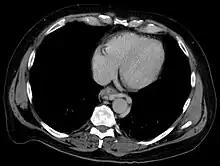

The upper two thirds of the esophagus are drained via the esophageal veins, which carry deoxygenated blood from the esophagus to the azygos vein, which in turn drains directly into the superior vena cava. These veins have no part in the development of esophageal varices. The lower one third of the esophagus is drained into the superficial veins lining the esophageal mucosa, which drain into the left gastric vein, which in turn drains directly into the portal vein. These superficial veins (normally only approximately 1 mm in diameter) become distended up to 1–2 cm in diameter in association with portal hypertension.

Normal portal pressure is approximately 9 mmHg compared to an inferior vena cava pressure of 2–6 mmHg. This creates a normal pressure gradient of 3–7 mmHg. If the portal pressure rises above 12 mmHg, this gradient rises to 7–10 mmHg.[5] A gradient greater than 5 mmHg is considered portal hypertension. At gradients greater than 10 mmHg, blood flowing through the hepatic portal system is redirected from the liver into areas with lower venous pressures. This means that collateral circulation develops in the lower esophagus, abdominal wall, stomach, and rectum. The small blood vessels in these areas become distended, becoming more thin-walled, and appear as varicosities.

In situations where portal pressures increase, such as with cirrhosis, there is dilation of veins in the anastomosis, leading to esophageal varices.[3] Splenic vein thrombosis is a rare condition that causes esophageal varices without a raised portal pressure. Splenectomy can cure the variceal bleeding due to splenic vein thrombosis.